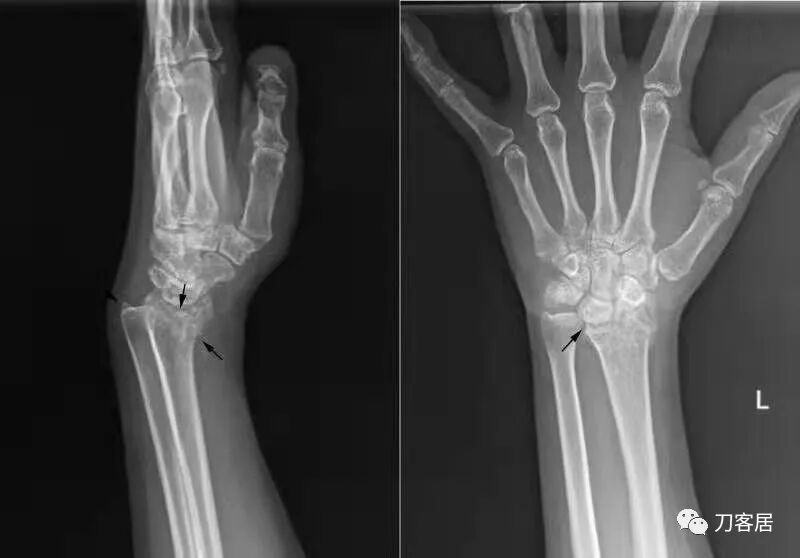

1.  这是一个很简单的6岁儿童无移位的尺桡骨远端骨折。没有皮肤损伤,没有移位,没有骨折碎块儿。

2.  这个骨折处理起来也很简单,单纯的打石膏托或者中医的小夹板,或者正规的包括腕关节和肘关节的管型石膏外固定4周即可治愈该骨折。实在不行,如果这个孩子比较听话,不太调皮的话,用一本书,一个三角巾悬吊固定4周,都可以治愈该骨折。但是给这个患者用外固定架做了手术,而且桡骨远端的几颗克氏针距离骨折线太近,其中一枚克氏针进入到骨折间隙内。从这个术中图片来看,术者的外固定手术技术也有待于进一步的提高。毕竟术者应该还很年轻。从X线片来看,前臂及手的尺侧有不透光影,应该还使用了外固定石膏绷带托,而且我猜测应该是高分子的石膏绷带托,这个是纯属猜测,不一定是对的,不过如何解释前臂尺侧的不透光影呢?如果真是用了石膏绷带外固定的话,那为啥要做手术呢?外固定架术后就不该再用石膏绷带托辅助了。

这个病例,6岁的孩子,尺桡骨骨折在同一个平面,且都为小斜行骨折,不是螺旋形,不是粉碎性,不是成角移位性,属于稳定性尺桡骨双骨折,根本就没有任何手术的适应症。